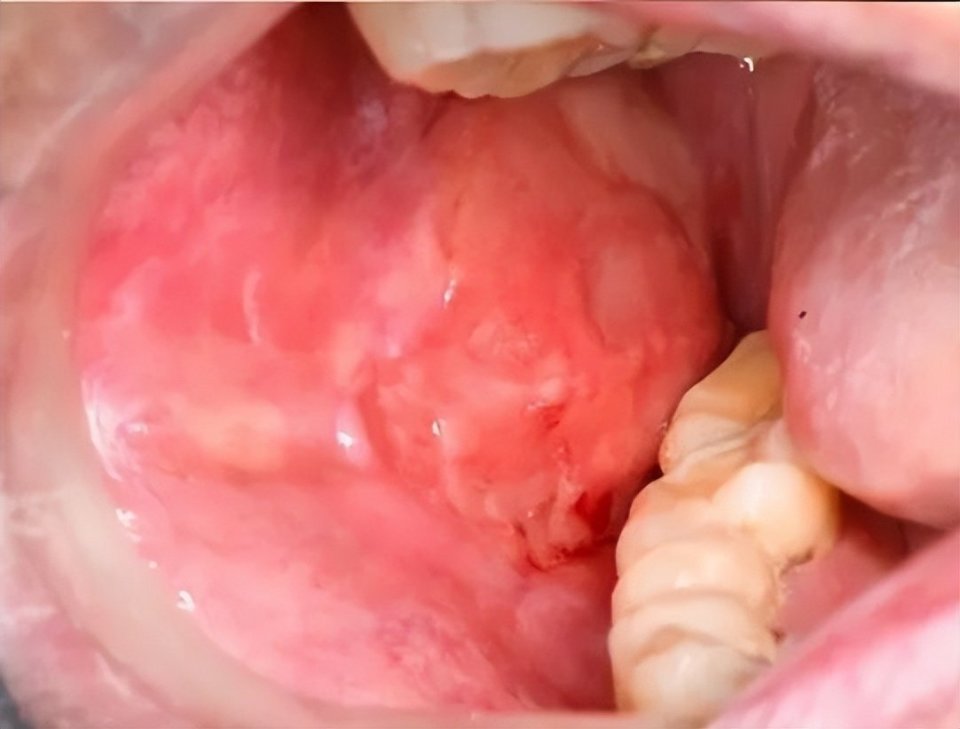

若患者表现为口干、黏液囊肿、黏膜萎缩、溃疡及假膜等症状,而无特征性改变,则需排除药物、感染、肿瘤等原因,并辅助组织病理学检查以明确诊断。

cGVHD口腔表现:红斑、苔藓样损害、溃疡及假膜形成(图片源自陶人川教授团队)